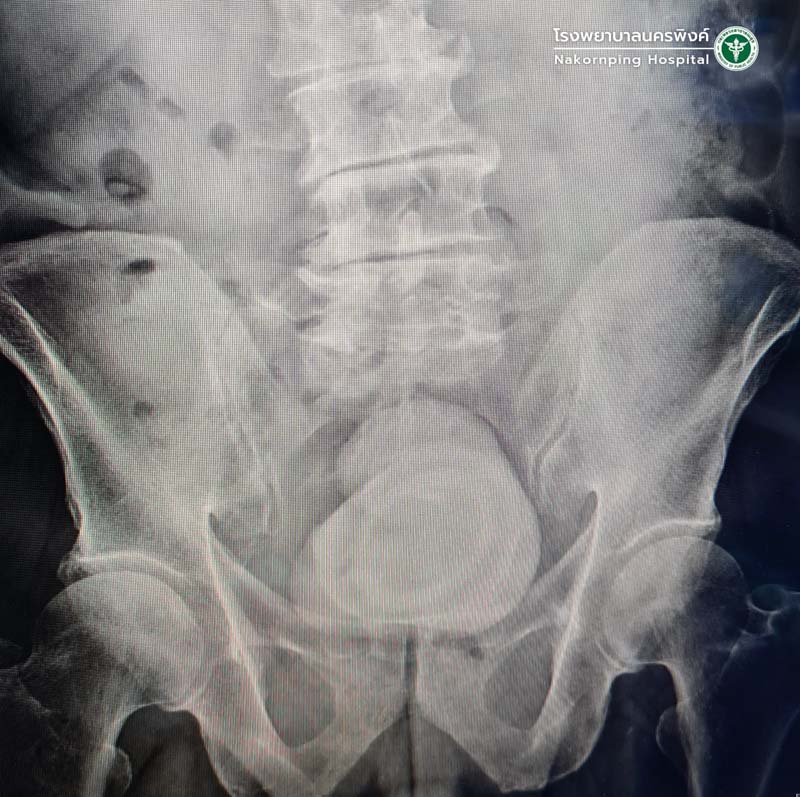

ผู้ป่วยชายอายุ 76 ปีมีอาการปัสสาวะแสบขัด ปวดท้องน้อย มีการติดเชื้อทางเดินปัสสาวะหลายครั้ง ส่งมารักษาที่แผนกศัลยกรรมระบบทางเดินปัสสาวะ รพ.นครพิงค์ ตรวจเอกซเรย์พบว่ามีนิ่วในกระเพาะปัสสาวะขนาดใหญ่ เส้นผ่านศูนย์กลางเกือบ 10 ซม. ศัลยแพทย์ระบบทางเดินปัสสาวะจึงได้ทำการผ่าตัดนิ่วในกระเพาะปัสสาวะออก พบว่านิ่วมีขนาดใหญ่น้ำหนักเกือบครึ่งกิโลกรัม หลังผ่าตัดผู้ป่วยปัสสาวะโล่งดี ไม่พบการติดเชื้อแล้ว

การวินิจฉัยนิ่วในกระเพาะปัสสาวะ สามารถทำได้จากการตรวจทางรังสี เช่น เอกซเรย์ อัลตราซาวด์ เอกซเรย์คอมพิวเตอร์ และการส่องกล้อง